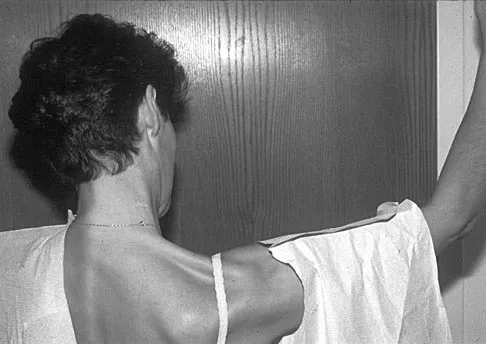

A 20-year-old-man sustained a scapular fracture after attempting to grab a beam as he fell through a ceiling at a job site 3 months ago. A clinical photograph is shown in Figure 36. He now reports pain in the anterior shoulder and difficulty with overhead activities. What nerve roots make up the involved peripheral nerve?

Explanation